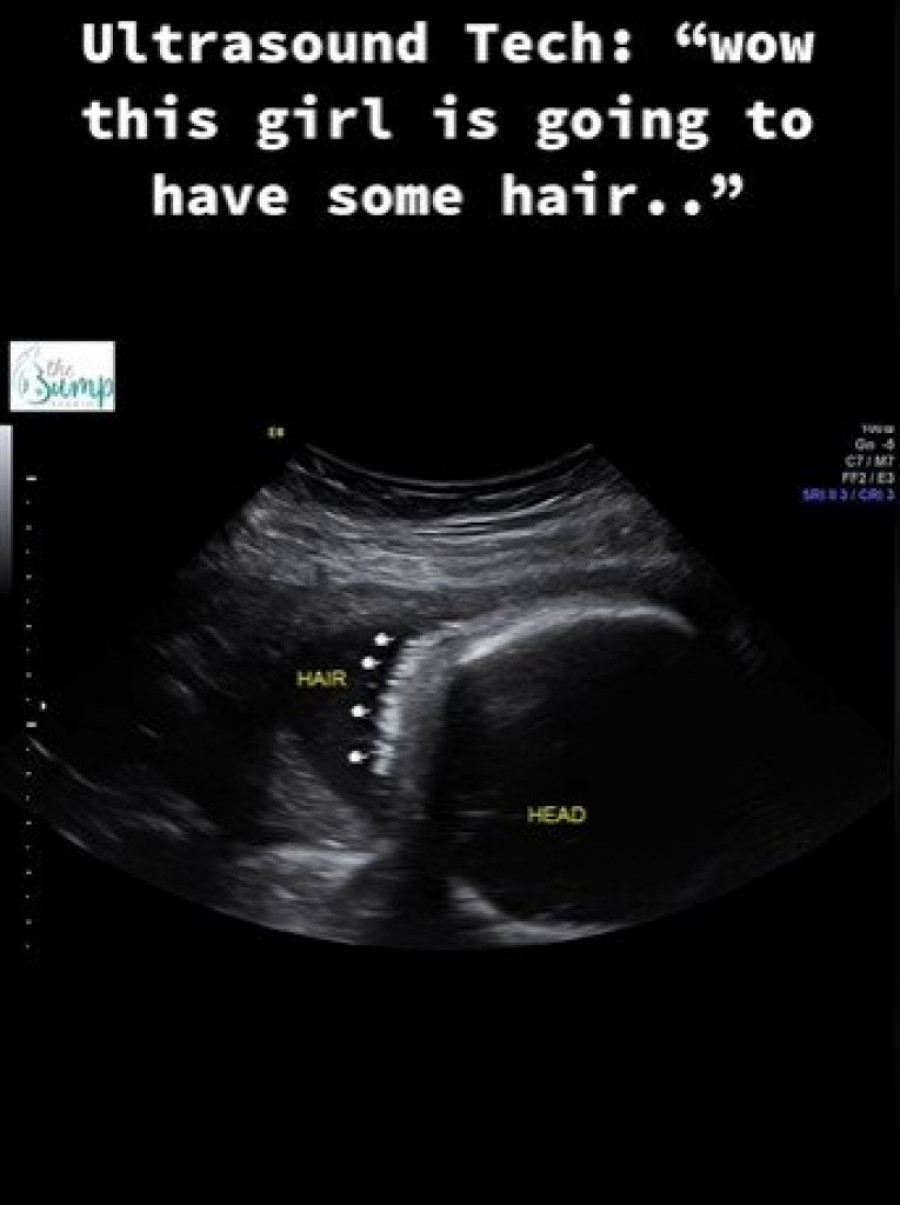

KADA JE OTIŠLA NA ULTRAZVUK ŠOKIRANO JE GLEDALA U OVU TAČKU: Zbunjena mama je na pregledu saznala šta je to, BACA U NEVERICU (VIDEO)

Pogledajte sliku sa ultrazvuka.

Džordan Filips je mama preslatke devojčice. Sve detalje napretka trudnoće, odlazak na preglede kao i sam porođaj, roditelji su podelili sa ljudima koji ih prate na društvenim mrežama. Oni su prošle godine išli na ultrazvuk kako bi pratili napredak devojčice. Pregled je bio zakazan 26. septembra 2023. godine. Tada su na ultrazvuku videli svoju devojčicu, ali i nešto drugo što im je privuklo pažnju.

Sliku sa ultrazvuka prikazali su i u videu na TikToku. Naime, devojčica je imala kosu koja je jasno bila obeležena strelicama. Nakon ovog videa, slede slike sa porođaja. Tek tada, kosa je zaista bila primetna i mnogi su bili oduševljeni kako je lepa, gusta i crna.

- Ova devojčica je zapravo rođena sa baš malo kose - napisala je ironično majka devojčice u opisu videa na TikToku.